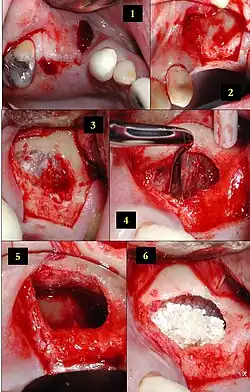

Lateral window technique

The lateral (traditional) approach creates a window in the sinus wall, lifts the membrane, and places graft material. Healing usually takes 4–12 months.[8]

Bone substitutes include autograft, allograft, xenograft, and alloplast.[9] Long-term success exceeds 90%.[10]